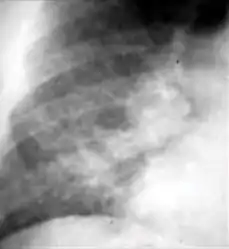

Chest x-ray showing nodule with margins that are indistinct or poorly defined (tree-in-bud sign) in post-primary pulmonary TB.